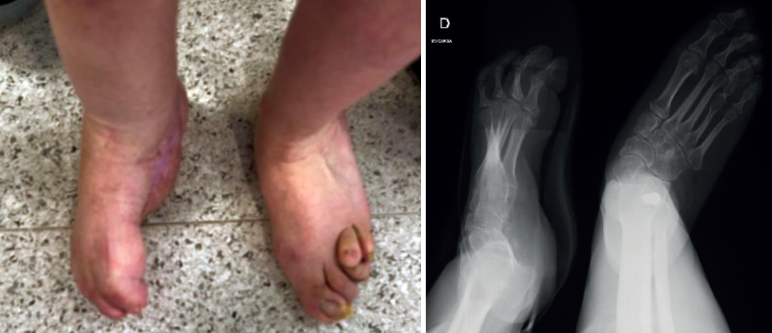

Se trata de una paciente de 34 años en seguimiento en consultas externas por pie zambo derecho congénito. Presenta un tobillo, mediopié y antepié rígidos, un pie equino, varo, aducto y supinado rígido (Figura 1), además de anestesia sensitiva (a consecuencia de lipomeningocele).

Sus dedos menores se encuentran en ráfaga media y presenta úlceras periódicas en la base de M5 por hiperapoyo (Figura 2). Además, la paciente nunca había tenido un pie plantígrado.